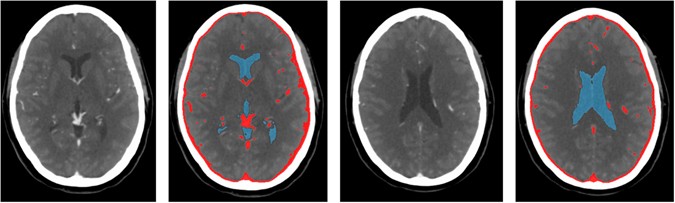

Figure 6

Examples of CSF and vessel segmentation using intensity information and morphological operations in the WTA image (window level/width 100/300 HU). These structures are masked in the intracranial image before WM and GM segmentation.